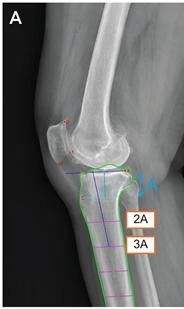

[사진 : 딥러닝 모델의 측정 매커니즘. 6개의 해부학적 기준점(빨간 점)을 자동 인식한 후, 경골의 관절선과 중심축(파란 선)을 결정해 경골 후방 기울기를 계산한다.]

이 모델은 무릎뼈의 6개의 해부학적 기준점(랜드마크, 해부학적 기준점: 슬개골 상·하단 극, 슬개골 관절면 원위부 가장자리, 내측 경골 고원 전·후방 정점, 경골 결절의 근위부)을 자동으로 인식한다.

이후 각 기준점을 이용하여 경골의 관절선과 중심축을 결정하고, 이를 바탕으로 기울기를 계산한다. 이 방법은 엑스레이 영상이 짧거나, 실제 거리 측정이 불가능한 경우 등 다양한 임상 조건에서 활용 가능하다는 장점이 있다.